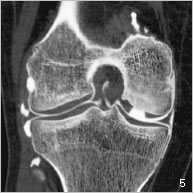

Une lésion cartilagineuse peut survenir lors d’un choc, à la suite de petits traumatismes répétitifs, ou à la suite d’une imperfection de la croissance. Le cartilage ainsi abîmé se décolle seul de son emplacement naturel ou accompagné d’une petite partie osseuse sous-jacente (figures 2 et 5). Il peut se détacher partiellement sous forme d’un clapet, ou bien complètement constituant ainsi un fragment libre. La zone de défect cartilagineux peut être plus ou moins étendue et plus ou moins profonde. La lésion cartilagineuse peut occasionner des douleurs, des blocages, des gonflements voire des sensations d’instabilité. Des lésions ligamentaires ou méniscales peuvent être associées.

Une ou plusieurs carottes ostéo-cartilagineuses sont prélevées à partir d’une zone peu sollicitée en périphérie du fémur à l’aide d’un instrument spécifique (figure 3). L’os du défect est préparé pour recevoir la greffe. Enfin, les carottes ostéo-cartilagineuses sont impactées côte à côte comme une vraie mosaïque pour reformer une surface de glissement homogène (figures 4, 6 et 7).